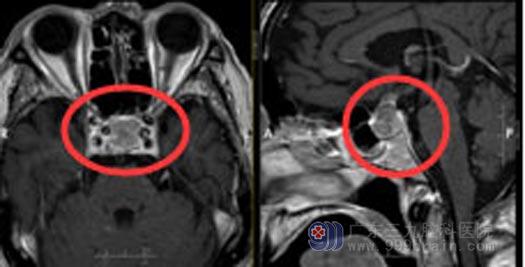

最近几天,孔大爷不仅是眼睛不好使,偶尔还会有头痛,在当地医院进行检查,发现“鞍区占位合并卒中”。由于当地医院的条件有限,孔大爷在家人陪伴下来到了广东三九脑科医院神经外五科,初步诊断:鞍区占位性病变,考虑垂体瘤。

医院副院长、神经外五科主任鲁明查阅了孔大爷的影像资料后,告诉他们:视力下降是肿瘤压迫视神经引起,并且肿瘤已经卒中,只有手术治疗才能根治。家人有点担心,大爷已是高龄,能否耐受开颅手术?